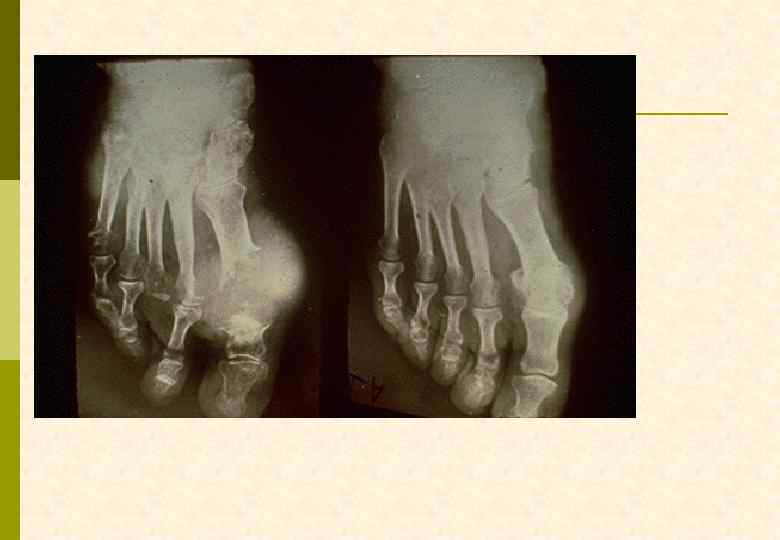

Не только подагра трогает первые пальцы мужских стоп. . .